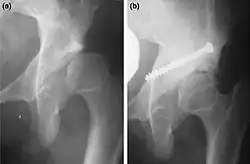

a. X-ray of a hip after capsulorrhaphy and Dega surgery.

b. Same hip after addition of Chiari medial displacementosteotomy.[4]

Adjustments are made to part of the hip-bone. Many operating methods and variations have been developed. They are defined by the type of cut and adjustment made. Some acetabular procedures are named after the surgeons who first described them as Salter (R. Salter), Dega (W. Dega), Sutherland (D.H. Sutherland), Chiari (K. Chiari): other names one may encounter are Ludlov, P. Pemberton, and James B. Steele. Some are named after the shape of cut (e.g. Chevron, Wedge) or the way the bones are aligned (Dial=old style rotary dial phone).